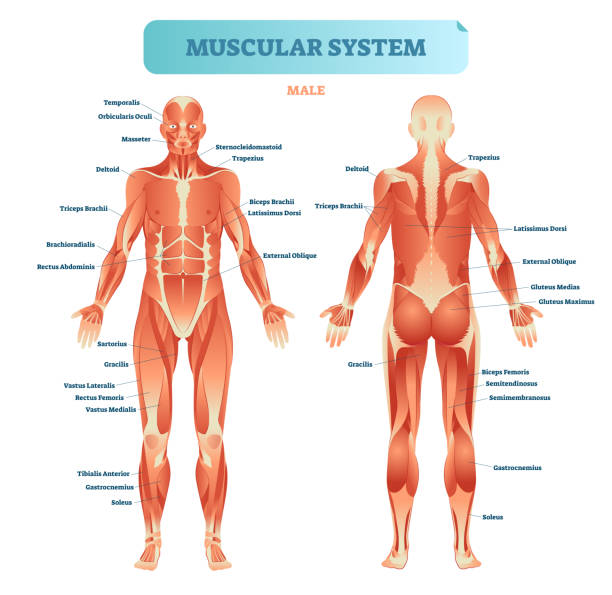

How does the sartorius muscle function during activities like getting in and out of a car?

what does sartorius muscle do Informational